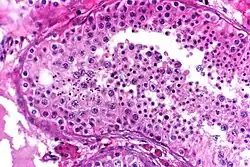

Seminiferous tubule with maturing sperm. H&E stain. | |

Spermatogenesis starts in the bottom part of seminiferous tubes and, progressively, cells go deeper into tubes and moving along it until mature spermatozoa reaches the lumen, where mature spermatozoa are deposited. The division happens asynchronically; if the tube is cut transversally one could observe different maturation states. A group of cells with different maturation states that are being generated at the same time is called a spermatogenic wave.[5]

Spermatocytogenesis

Spermatocytogenesis is the male form of gametocytogenesis and results in the formation of spermatocytes possessing half the normal complement of genetic material. In spermatocytogenesis, a diploid spermatogonium, which resides in the basal compartment of the seminiferous tubules, divides mitotically, producing two diploid intermediate cells called primary spermatocytes. Each primary spermatocyte then moves into the adluminal compartment of the seminiferous tubules and duplicates its DNA and subsequently undergoes meiosis I to produce two haploid secondary spermatocytes, which will later divide once more into haploid spermatids. This division implicates sources of genetic variation, such as random inclusion of either parental chromosomes, and chromosomal crossover that increases the genetic variability of the gamete. The DNA damage response (DDR) machinery plays an important role in spermatogenesis. The protein FMRP binds to meiotic chromosomes and regulates the dynamics of the DDR machinery during spermatogenesis.[13] FMRP appears to be necessary for the repair of DNA damage.

Spermatidogenesis

Spermatidogenesis is the creation of spermatids from secondary spermatocytes. Secondary spermatocytes produced earlier rapidly enter meiosis II and divide to produce haploid spermatids. The brevity of this stage means that secondary spermatocytes are rarely seen in histological studies.

Role of Sertoli cells

At all stages of differentiation, the spermatogenic cells are in close contact with Sertoli cells which are thought to provide structural and metabolic support to the developing sperm cells. A single Sertoli cell extends from the basement membrane to the lumen of the seminiferous tubule, although the cytoplasmic processes are difficult to distinguish at the light microscopic level.